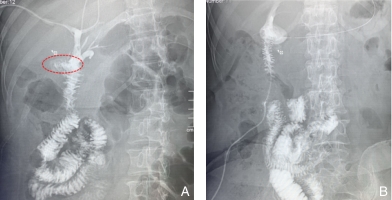

图2 第2次入院影像学资料 A:腹部增强CT动脉期可见肝右动脉侧支循环(箭头所示);B:上腹部MRCP可见右肝前叶萎缩,胆管扩张,左肝代偿性增大;C:术前造影仍示三支分离(右前叶肝管、右后叶肝管及左肝管)(箭头所示),同时可见肝门与椎体右缘距离增宽,提示肝门逆钟向转位Fig.2 Imaging findings at the second admission A: Enhanced CT of the abdomen in the arterial phase shows collateral circulation of the right hepatic artery (arrow); B: Upper abdominal MRCP demonstrates atrophy of the right anterior lobe of the liver, dilated bile ducts, and compensatory hypertrophy of the left liver; C: Preoperative cholangiography still shows separation of three branches (right anterior hepatic duct, right posterior hepatic duct, and left hepatic duct) (arrow), with widening of the distance between the hepatic hilum and the right margin of the vertebral body, suggesting retrograde clockwise transposition of the hilum